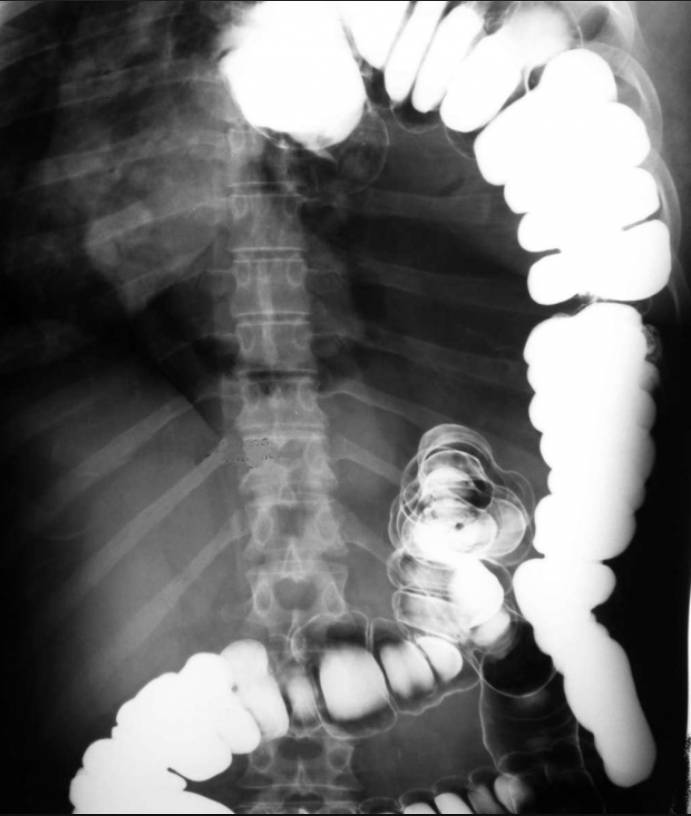

The chest radiography showed a radiopaque left hemithorax with right shift of the mediastinum. Double-contrast barium enema demonstrated the presence of large part of the intestine inside the left hemithorax (image below).

CT examination revealed complete occupation of the left hemithorax by abdominal organs. Namely, the left hemithorax contained the spleen, small and large intestine and a large quantity of mesenteric fat. The small and large intestine lied in the periphery of the thoracic cavity while its central part was occupied by mesenteric fat.

CT also revealed a hypoplastic left lung, the presence of left pulmonary artery and a blind-ended left main bronchus. Finally, the CT examination demonstrated a defect in the left hemidiaphragm, which caused the intrathoracic displacement of the abdominal organs.